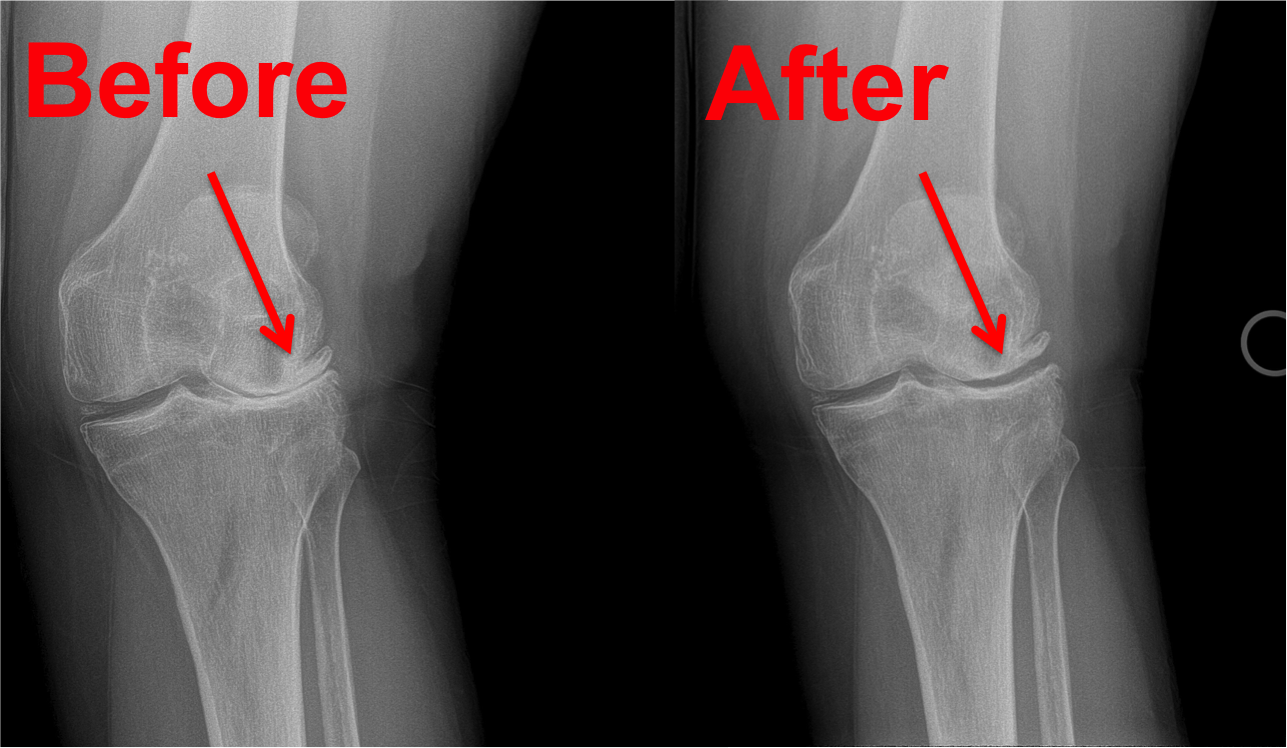

Regenerative Stem Cell Therapy provides a high concentration of stem cells in its application. This concentration equips the body to repair damage, reduce inflammation, and alleviate both chronic and acute pain related to joint conditions.

Unlike many other treatments, stem cell therapy actually helps the body to heal damage to your joints instead of masking pain or using artificial means, like steroids or drugs, to reduce inflammation.

Regrow Cells In Damaged Areas With Stem Cell Therapy